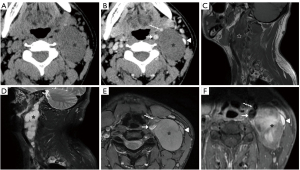

Paragangliomas have characteristic CT and MRI appearances based on their hypervascularity. They are usually homogeneously or heterogeneously hyperdense or hyperintense after contrast enhancement, with incorporation of adjacent arteries on CT and MRI (Figures 10-12) (12). On MRI, serpentine and punctate areas of signal void representing high vascular flow are interspersed with areas of high signal intensity caused by slowly flowing blood. This “salt-and-pepper” pattern is seen in all lesions greater than 2 cm in maximal dimension (Figure 11) (23-25). Carotid body tumors (paragangliomas of the carotid body) splay the ICA and the external carotid artery (ECA) and may encase the ICA and ECA (Figure 10), whereas vagal paragangliomas displace both ICA and ECA anteromedially, separating these vessels from the IJV (Figure 11). Paragangliomas may be multicentric and can manifest as unilateral or bilateral lesions, either simultaneously or sequentially. Only a very low percentage of 3% of paragangliomas will undergo malignant transformation (25). The presence of local lymph node involvement, distant metastases, or extensive local invasion will establish the malignancy of a paraganglioma.

In the past, digital subtraction angiography (DSA) played an important role as a first-line imaging investigation for paragangliomas (26). However, such an invasive method is reserved for those few patients whose diagnosis, after sectional imaging, remains inconclusive, or preoperative embolization. DSA, and sometimes computed tomography angiography (CTA), will show feeding arteries, such as the ascending pharyngeal artery (the artery of the paraganglioma) (Figure 12) and occipital artery (27). DSA also shows intense staining of the tumor and a rapid venous drainage.